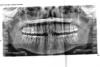

Ирина12 Опубликовано 9 ноября, 2009 Автор Поделиться Опубликовано 9 ноября, 2009 (изменено) снимок Изменено 9 ноября, 2009 пользователем oconnor Ссылка на комментарий

Андрей Опубликовано 9 ноября, 2009 Поделиться Опубликовано 9 ноября, 2009 снимокПо снимку парадонтита не видно, зато видно, что надо перелечивать каналы в верхнем правом шестом зубе. А еще у Вас верхние боковые резцы стерлись. Ссылка на комментарий

Андрей Опубликовано 9 ноября, 2009 Поделиться Опубликовано 9 ноября, 2009 а как же оголение корней...? или это что-то еще?а без "перелечивать" нельзя? после смены замены старой пломбы я у трех врачей пыталась новую шлифовала-отдавало в десну... а что с клыками делать? так вроде они есть....По снимку не видно оголенной десны, гентген не показываеи, мягки ткани. Сделайте обычное фото, только четкое.Перелечивать по хорошему нужно, а зуб тот нужно коронкой покрыть, а не пломбой восстанавливать, так он дольше простоитюСтерты у Вас не клыки, а вторые зубы от цетра. Это резцы. Нужно их видеть, чтоб понять нужно ли с ними чего делатьили не нужно. Ссылка на комментарий